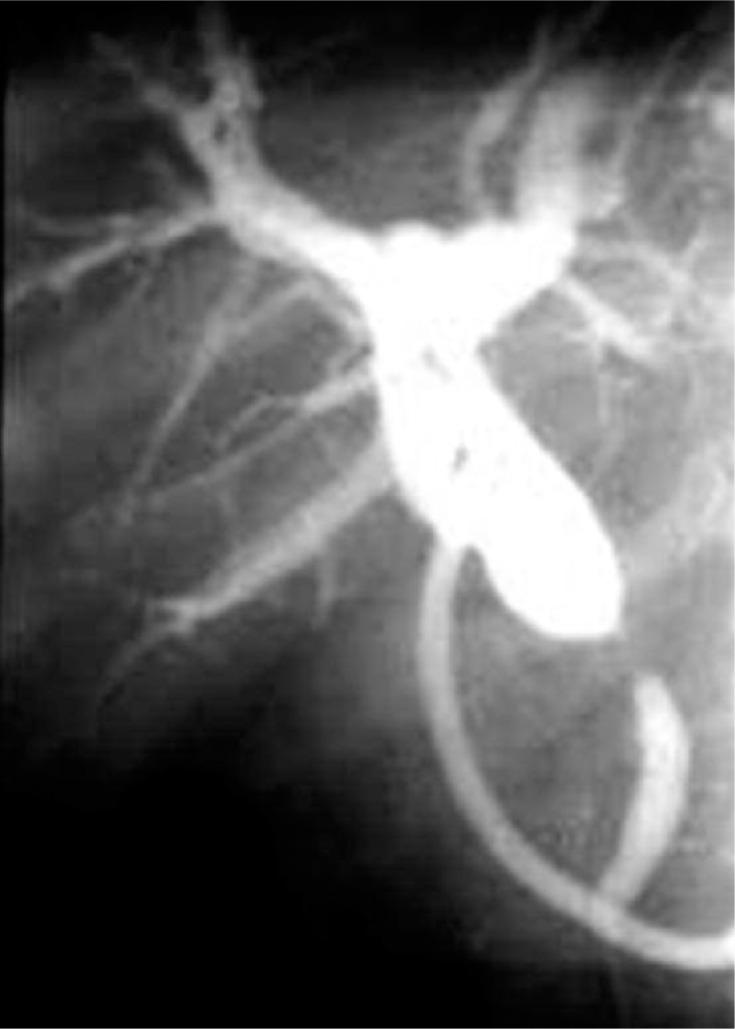

Pancreatobiliary and peripancreatobiliary tuberculosis: a rare cause of obstructive jaundice.

Arch Med Sci. 2013 Dec 30;9(6):1152-7. doi: 10.5114/aoms.2013.39799. Epub 2013 Dec 26.